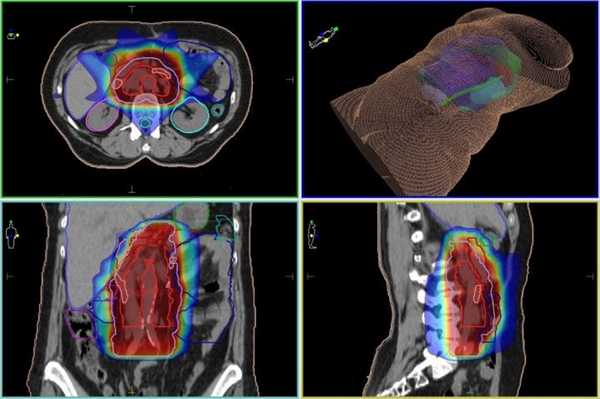

В случае наличия множественных метастазов пациенту показана химиотерапия, а для лечения единичных метастазов в мировой практике широко применяется высокоточная лучевая терапия IMRT. Также, лучевая терапия комбинируется с хирургическим лечением первичной опухоли, после которого большинство мировых протоколов предусматривают облучение ложа удаленной опухоли и лимфоузлов.

Метастазы в лимфоузлы брюшной полости и забрюшинного пространства, план лучевой терапии IMRT на современном линейном ускорителе

Однозначной рекомендации том, что любой метастаз в лимфоузел подлежит лечению на КиберНоже, не существует. В ряде случаев лечение метастазов в лимфоузлы брюшной полости, забрюшинного пространства и малого таза большей эффективности можно добиться радикальным лечением на высокоточном линейном ускорителе (IMRT). Поэтому, как и любое другие лечение, радиохирургия на КиберНоже для метастазов в лимфоузлы назначается после проведения междисциплинарного консилиума, на котором врачи различных специализаций рассматривают все аспекты конкретного случая с тем, чтобы определить максимально эффективную схему лечения.

Если пациенту показана радиохирургия на КиберНоже, проводится предварительное планирование, во время которого на основание данных КТ- и МРТ-диагностики будет создана объемная модель взаимного расположения пораженного лимфатического узла, окружающих его здоровых тканей, а также будет учтены расположенные вблизи структуры организма, в которые недопустима подача ионизирующего излучения.

Во время каждого из сеансов лечения (фракций) КиберНож на основании плана лечения подаст множество одиночных пучков ионизирующего излучения, на пересечении которых будет сформирована зона высокой дозы, отвечающая форме и объему метастаза в лимфатический узел. Кроме того, лечение метастазов на КиберНоже может включаться в состав фракции (сеанса) по лечению первичной опухоли или других метастазов.